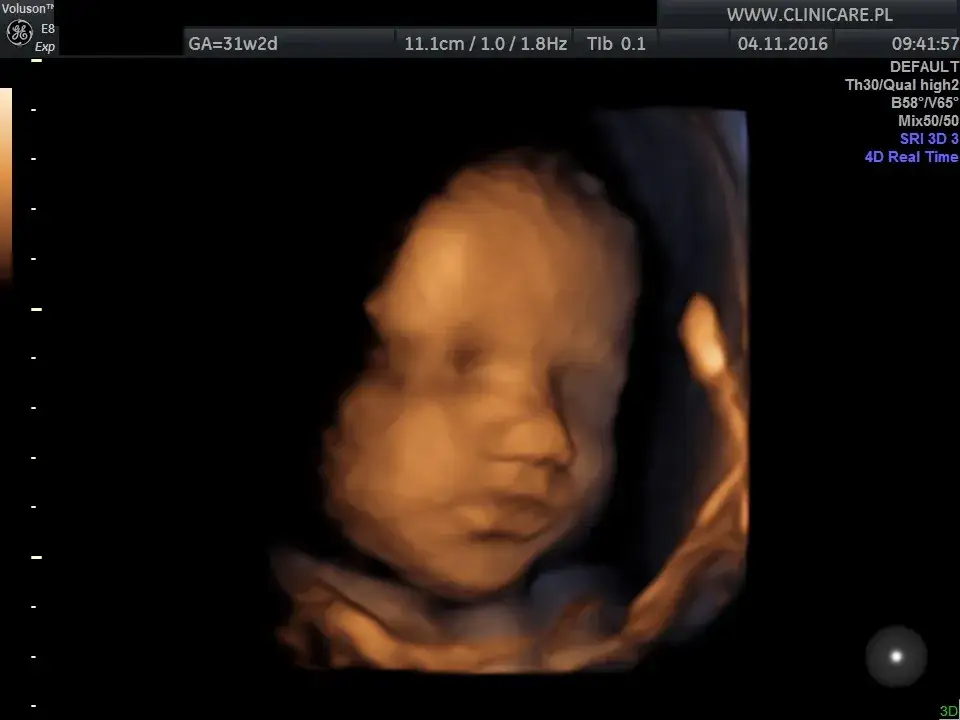

Dowiedz się, kiedy wykonać 3. USG prenatalne (28-32 tydz.). Sprawdź, co ocenia lekarz i jak się przygotować do badania.